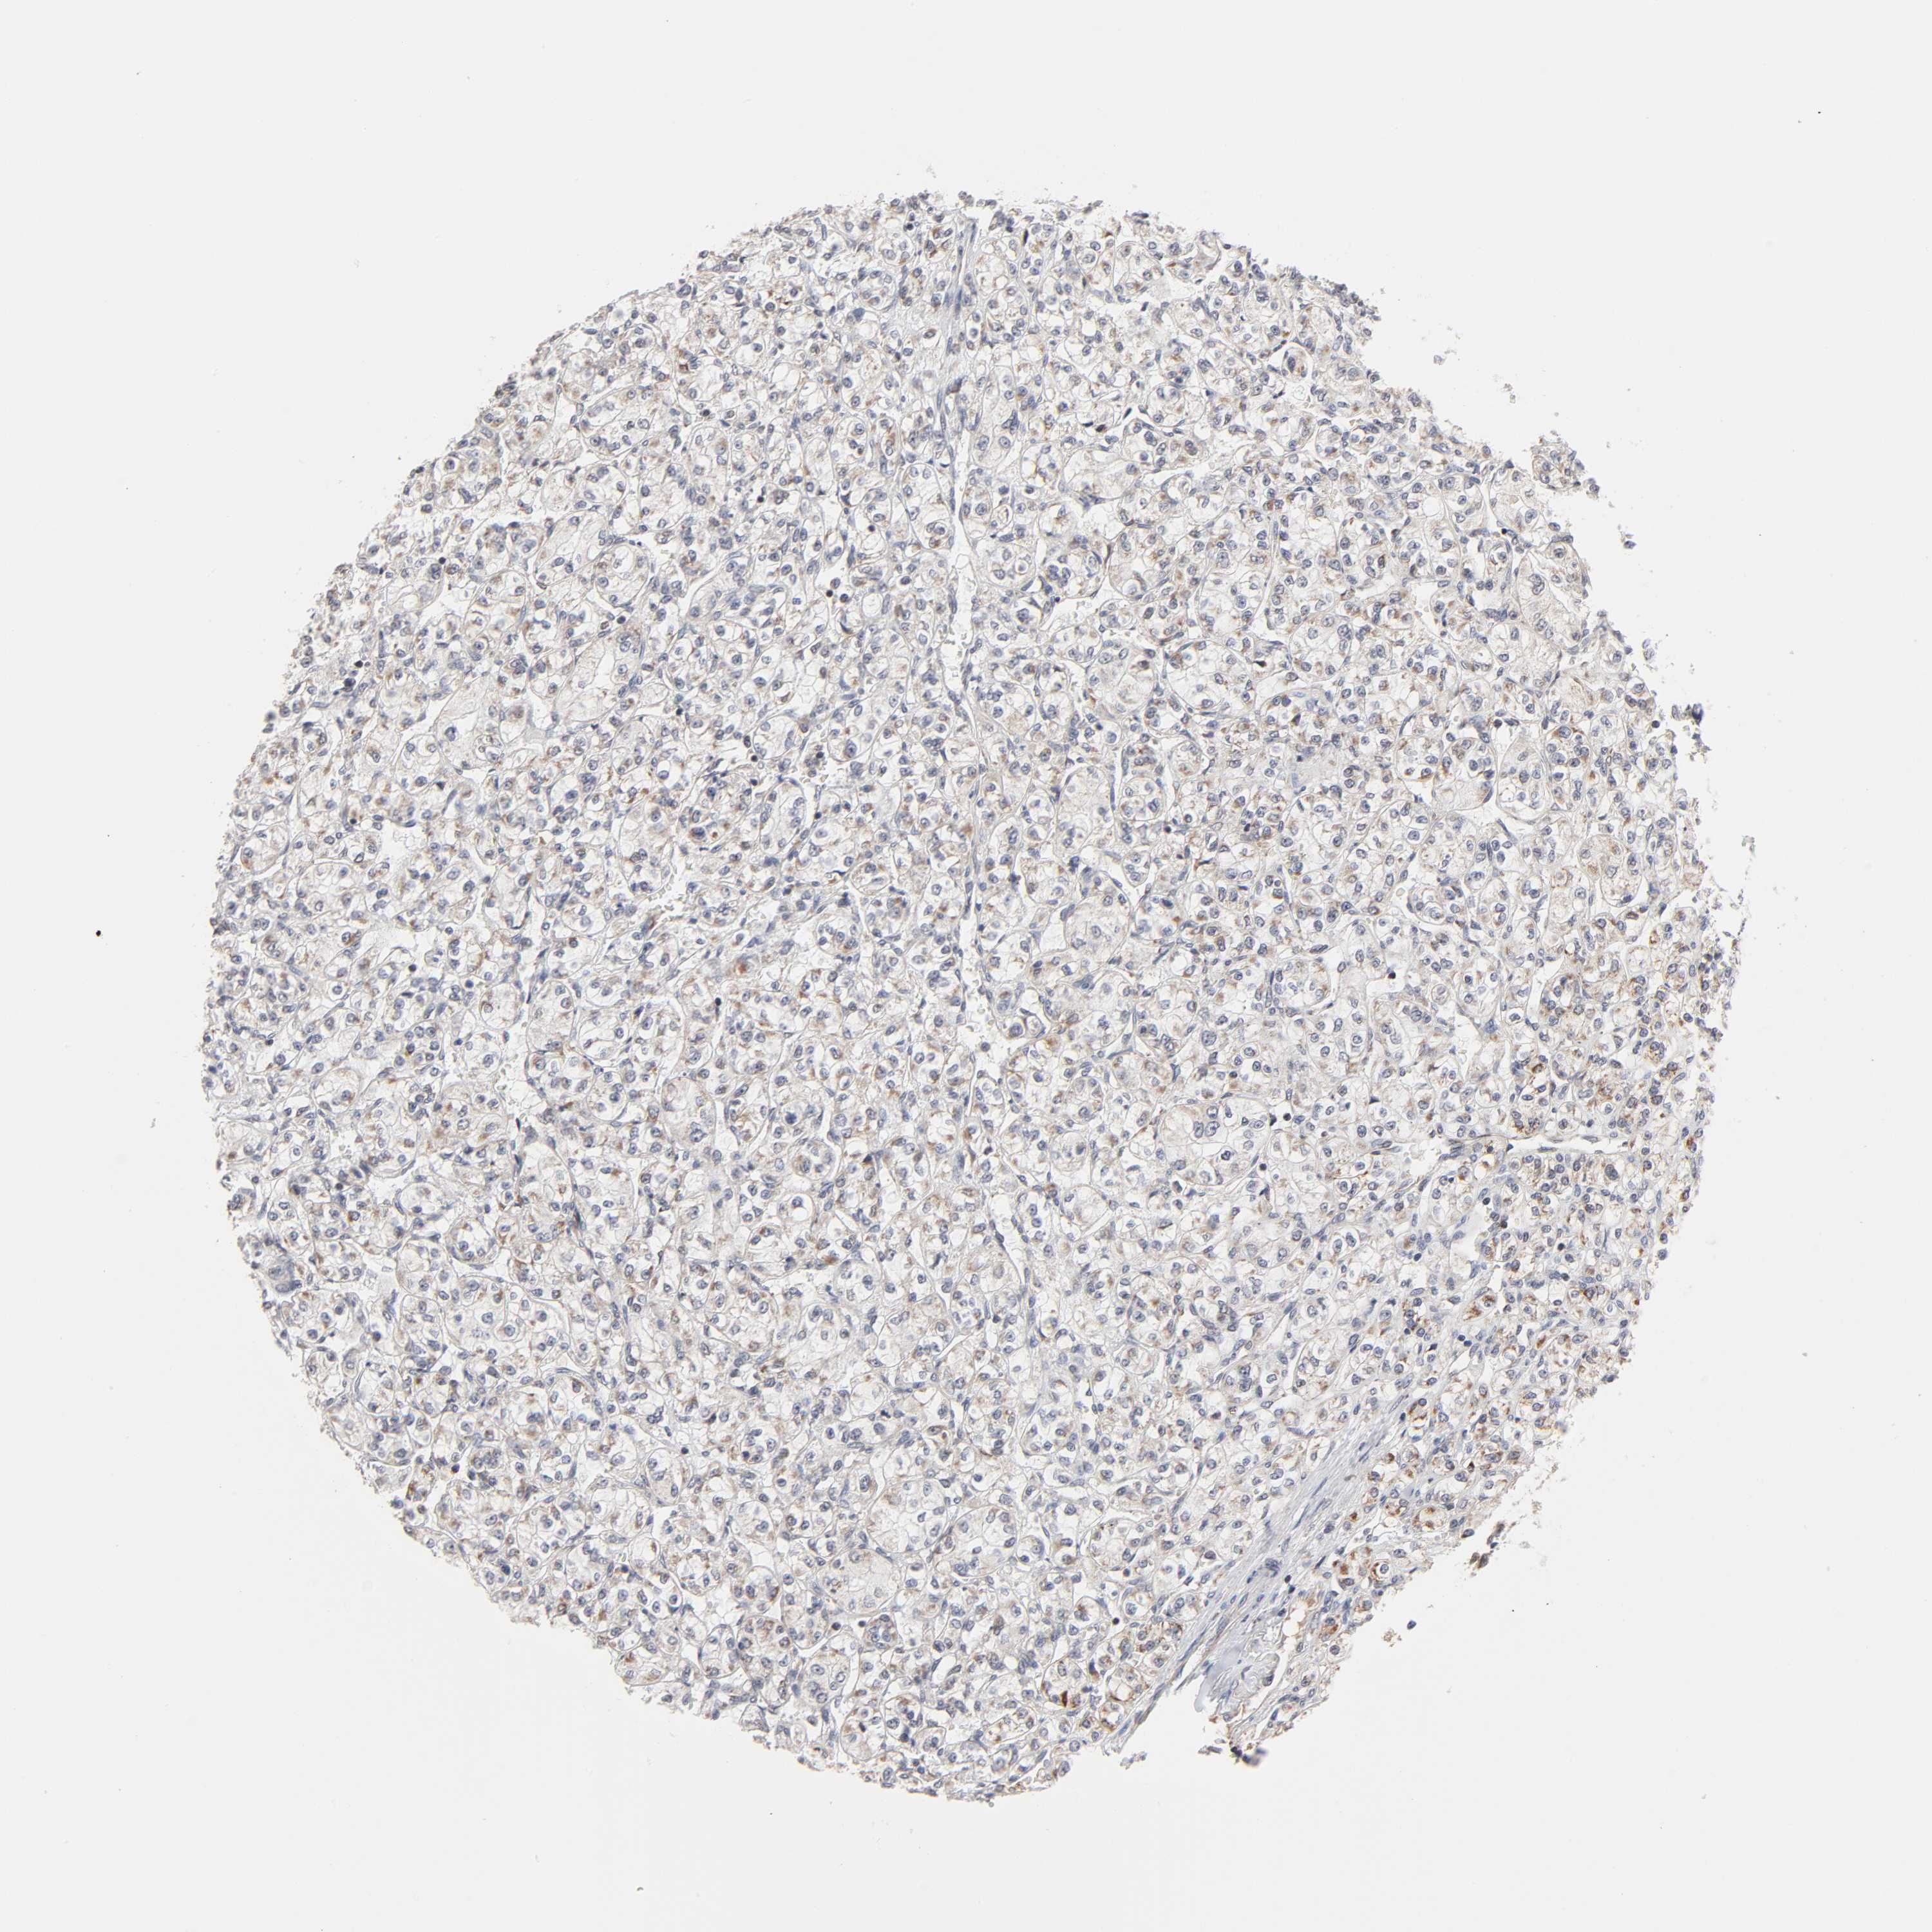

KIDNEY RENAL CLEAR CELL CARCINOMA (TCGA) - Interactive survival scatter ploti

The Survival Scatter plot shows the clinical status (i.e. dead or alive) for all individuals in the patient cohort, based on the same data that underlies the corresponding Kaplan-Meier plots. Patients that are alive at last time for follow-up are shown in blue and patients who have died during the study are shown in red.

The x-axis shows the expression levels (FPKM) of the investigated gene in the tumor tissue at the time of diagnosis. The y-axis shows the follow-up time after diagnosis (years). Both axes are complimented with kernel density curves demonstrating the data density over the axes. The top density plot shows the expression levels (FPKM) distribution among dead (red) and alive patients (blue). The right density plot shows the data density of the survived years of dead patients with high and low expression levels respectively, stratified using the cutoff indicated by the vertical dashed line through the Survival Scatter plot. This cutoff is automatically defined based on the FPKM cutoff that minimizes the p-score. The cutoff can be changed by dragging the vertical line or by entering a cutoff value in the square labeled "Current cut-off".

Under the Survival Scatter plot the p-score landscape (black curve; left axis) is shown together with dead median separation (red curve; right axis). Dead median separation is the difference in median mRNA expression between patients who have died with high and low expression, respectively. It is calculated as follows: median FPKM expression of dead patients with high expression - median FPKM expression of dead patients with low expression. This is intended to aid the user in visually exploring custom cutoffs and the associated p-scores and dead median separation.

Individual patient data is displayed and can be filtered by clicking on one or more of the category buttons on the top of the page. Categories describing expression level and patient information include: high, low, alive, dead, female, male and tumor stages. The scale of the x-axis can be toggled between linear and log-scale by clicking on the "x log" button. Mouse-over function shows TCGA ID, patient information and mRNA expression (FPKM) for each patient.

& Survival analysisi

Kaplan-Meier plots summarize results from analysis of correlation between mRNA expression level and patient survival. Patients were divided based on level of expression into one of the two groups "low" (under cut off) or "high" (over cut off). X-axis shows time for survival (years) and y-axis shows the probability of survival, where 1.0 corresponds to 100 percent.

AUH is validated prognostic, high expression is favorable in Kidney Renal Clear Cell Carcinoma (TCGA)

: 19.89

Average pTPM 21.8

Number of samples 521